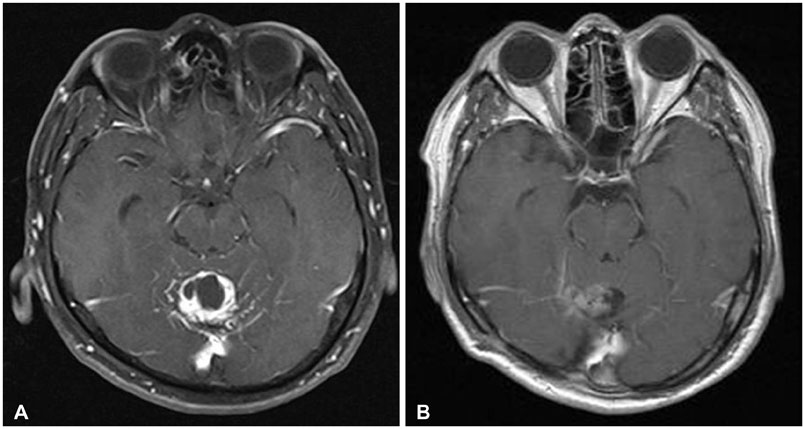

- Hemangioblastoma (HB) of the central nervous system may occur sporadically or in association with von Hippel-Lindau (VHL) disease. Disseminated HB means malignant spread of the original primary HB without local recurrence at surgically resected site. It has been rarely reported previously, and rarer especially without VHL gene mutation. We report a case of disseminated HB without VHL disease. A 59-year-old man underwent a surgery for total removal of a cerebellar HB. From five years after the surgery, multiple dissemination of HB was identified intracranially and he subsequently underwent cyberknife radiosurgery. The lesions got smaller temporarily, but they soon grew larger. Nine years after the initial surgery for cerebellar HB, he showed severe back pain. His magnetic resonance image of spine revealed intradural extramedullary mass at T6-7 level. Complete surgical removal of the mass was performed and the pathological diagnosis was identical to the previous one. He had no evidence of VHL disease. And there was no recurrence of the tumor at the site of the original operation. The exact mechanism of dissemination is unknown, but the surgeon should be cautious of tumor cell spillage during surgery and prudently consider the decision to perform ventriculo-peritoneal shunt. In addition, continuous follow-up for recurrence or dissemination is necessary for patients even who underwent complete removal of cerebellar HB.